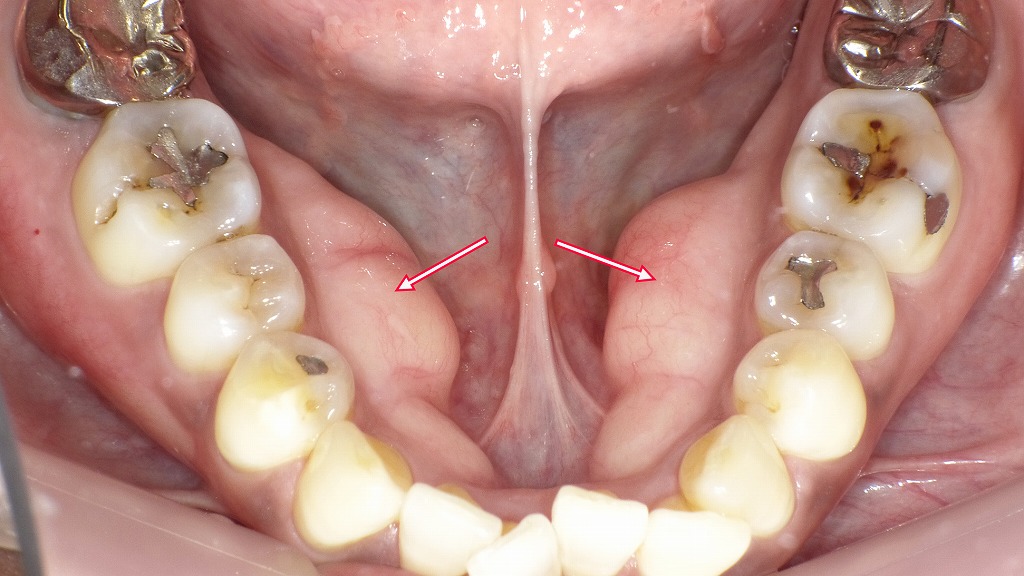

◆下顎前歯の唇側に多発した骨隆起

画像では、下顎の歯ぐき(舌側ではなく外側=唇側)に、白っぽく盛り上がった硬い膨らみが複数みられます。

赤矢印で示されている部分は、**骨が局所的に厚く発達した「骨隆起(こつりゅうき)」**です。

◆特徴

- 左右対称に複数みられることが多い

- 表面の粘膜は健康的な薄いピンク色

- 膨らみは硬く、触れても痛みはない(通常)

- 加齢や咬合力、歯ぎしり・食いしばりが関与することが多い

◆医学的な位置づけ

❏ 発生しやすい部位

- 下顎前歯部の舌側にできるもの:下顎隆起(Mandibular torus)

- 上顎正中部にできるもの:口蓋隆起

- まれに今回のように、下顎前歯の唇側(外側)に生じるケースもあります。